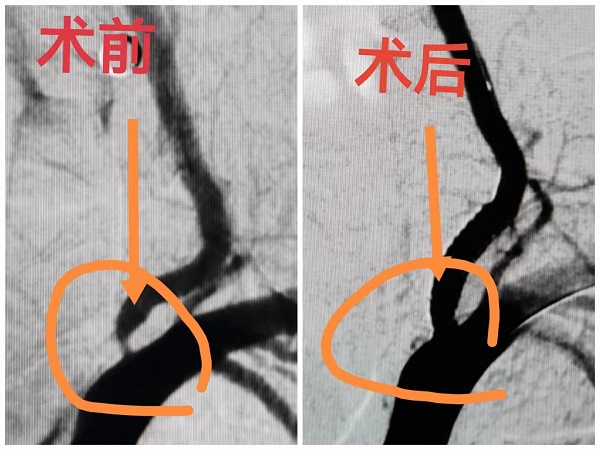

病例:患者男性,67岁,诊断“脑梗死、高血压、糖尿病、冠心病”,颈动脉彩超提示左侧颈动脉起始段狭窄,为进一步明确脑血管情况,预行脑血管造影;患者同时合并冠心病,提出希望能在脑血管造影同时,同台行冠脉造影明确心脏血管情况;为满足患者需求,我院神经内科立即请心血管内科医师会诊评估,最后决定为患者同台行冠脉及脑血管造影,造影顺利完成,精准评估了患者心脑血管狭窄程度,制定后期治疗计划,造影耗时约1.5小时,患者及家属非常满意。

心脏与脑血管造影手术是一种先进的影像学检查技术,通过向血管内注入造影剂,使心脏和脑血管显影,从而动态清晰地显示血管的形态、结构和血流情况。这种技术对于诊断血管狭窄、阻塞、动脉瘤等病变具有重要意义,并为后续的治疗提供精确的指导。

脑血管支架治疗